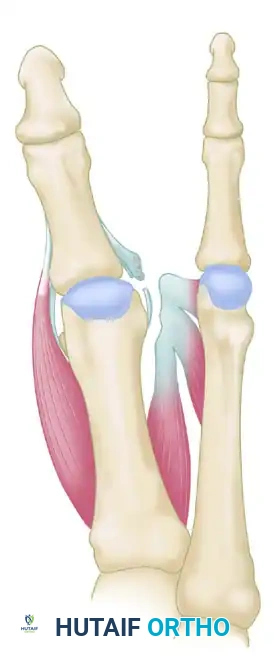

FIGURE 81-81A: Hallux varus secondary to severe intrinsic muscle imbalance. The abductor hallucis pulls the proximal phalanx medially due to the absence of lateral counter-forces.

Biomechanical Rationale

The Hawkins procedure neutralizes the deforming medial force by detaching the abductor hallucis and transferring it to act as a lateral stabilizer. Concurrently, the remnants of the lateral structures are advanced to restore the lateral moment arm.